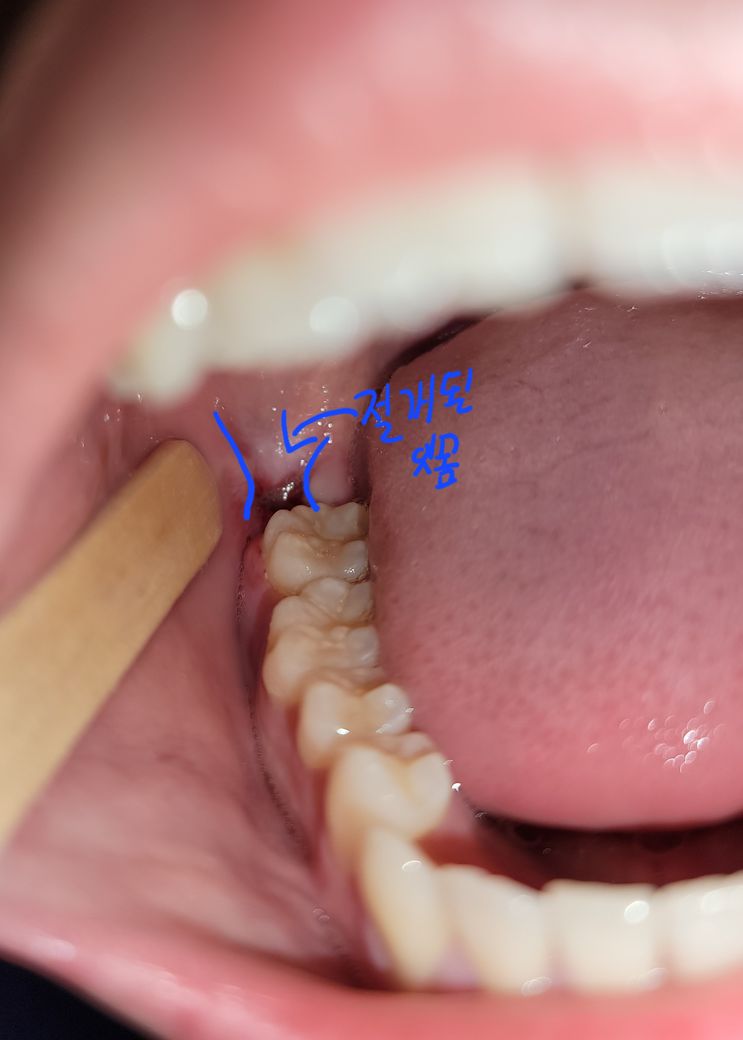

오늘 왼쪽도 뽑았는데 반대쪽에 비해 되게 깔끔하게 되어있어 반대쪽이 좀 이상해 보이더라고요.

• 3번 째 사진

완전히 닫히도록 매듭이 지어지지 않습니다. 현재 사진상 잘 낫고 있는 것으로 확인이 됩니다.

발치를 하고 나서는 해당 부위를 실밥으로 꼬메는 경우가 있습니다. 이 경우 잇몸이 완전히 접합되지 않은 상태도 있지만 버려져 있는 것보단 낫기 때문에 봉합을 하게 됩니다. 해당 부위에 음식물이 들어갈 수 있지만 음식물이 들어갔을 경우에는 가볍게 가글을 해주는 것이 좋습니다.

봉합과 상관없이 잇몸이 완전히 아물고 구멍이 없어지기 위해서는 1~2달 이상 걸리게 됩니다. 그 전까지는 음식물이 낀다면 치유에 방해가 될 수 있으므로 물로 가글을 살살해서 빼주거나 살살 양치질을 해주셔도 됩니다.